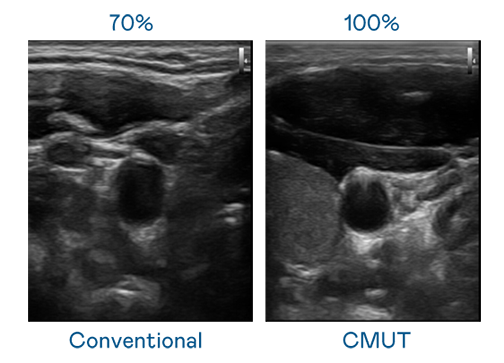

CMUT 技術是一種用電容式微機電元件來產生超音波訊號的技術。與傳統 PZT 壓電式技術相比,CMUT 頻寬增加 30%,更寬頻的超音波訊號讓影像解析度大幅提升,是實現高影像品質醫療超音波掃描、促進精準醫療發展的關鍵技術。

超音波影像的解析度高低,首先取決於探頭能發出的訊號頻寬。welcome海洋之神 CMUT 可提供高清晰的超音波訊號,提供高頻寬、高靈敏度、影像紋理細節更高的超音波影像,協助醫護人員縮短影像判讀時間及利用精準的醫療影像進行診斷。